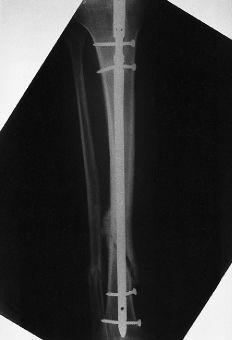

El tiempo medio operatorio fue de 63 minutos (mínimo: 45 y máximo: 90 minutos). Se utilizó un clavo de 8 mm en 29 casos y de 9 mm en 32; se produjo una fractura intraoperatoria de la cortical posterior (Fig. 1). La dinamización se llevó a cabo en una media de 9 semanas (mínimo: 5 y máximo: 20 semanas). La carga completa postoperatoria se inició a una media de 8 semanas (mínimo: 1 y máximo: 19 semanas) tras la intervención. Catorce (6,2%) de los 226 tornillos empleados se doblaron o rompieron (tres tornillos estáticos proximales, uno dinámico proximal y 10 tornillos distales). En tres pacientes el clavo no fue dinamizado antes de cargar peso. En uno de ellos se rompieron todos los tornillos y en dos se rompió el estático proximal y los dos distales (Fig. 2). En tres pacientes se rompieron los tornillos distales a pesar de que el clavo había sido dinamizado.

Cincuenta y ocho fracturas (95%) consolidaron en una media de 20 semanas (mínimo: 11 y máximo: 24 semanas). Hubo dos casos de retardo de consolidación que finalmente consolidaron en 31 y 33 semanas y uno de pseudoartrosis que ocurrió en una fractura Tipo B3 que se dinamizó 19 semanas tras el enclavado. Este paciente fue tratado mediante injerto óseo y enclavado fresado. Hubo una relación estadísticamente significativa (p < 0,01) entre la dinamización temprana (entre las 4 y 8 semanas tras el enclavado) y la consolidación precoz (12-16 semanas tras en enclavado).

Al final del seguimiento seis pacientes (9,8%) presentaron una angulación en valgo menor de 5° y 10 (16%) una angulación en valgo mayor de 5°. No hubo relación estadísticamente significativa entre la dinamización temprana (entre 4 y 8 semanas tras la fractura) o el tipo de fractura y la angulación en valgo, siendo la relación estadísticamente significativa entre el enclavado de 8 mm y la angulación en valgo mayor de 5° (p < 0,01).

Figura 1. Rotura intraoperatoria de la cortical posterior de la tibia.Postoperatoriamente no hubo ningún síndrome compartimental, infección, embolia grasa o complicación neurológica. Dos pacientes desarrollaron distrofia simpaticorrefleja, tres presentaron un acortamiento de 6-10 mm y 13 pacientes (21%) desarrollaron dolor femoropatelar que desapareció al retirar el clavo. Todos los pacientes presentaron una movilidad completa de la rodilla. Hubo cuatro casos de rigidez del tobillo con falta del 20% de extensión. Sesenta pacientes (98%) volvieron a caminar sin claudicación y sin bastones y a subir escaleras normalmente. Todos ellos recuperaron su nivel de actividad previa a la fractura.

Cuando los datos se analizaron de acuerdo a los criterios de Johner y Wruh hubo 39 (64%) pacientes con un resultado excelente, 11 (18%) con un resultado bueno, 10 (16%) con un resultado regular y uno con un resultado malo (Tabla 1).